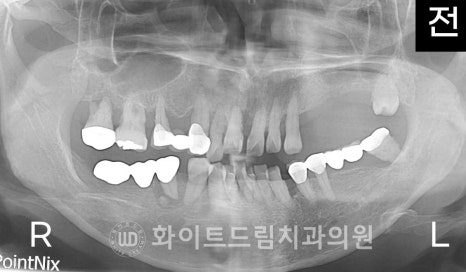

X-RAY 사진을 보면

전체적으로 잇몸뼈가 많이 녹아내려있고,

치아가 없는 오른쪽 상악 어금니 부위의 골 흡수가 크게 진행된 것을 보실 수 있습니다.